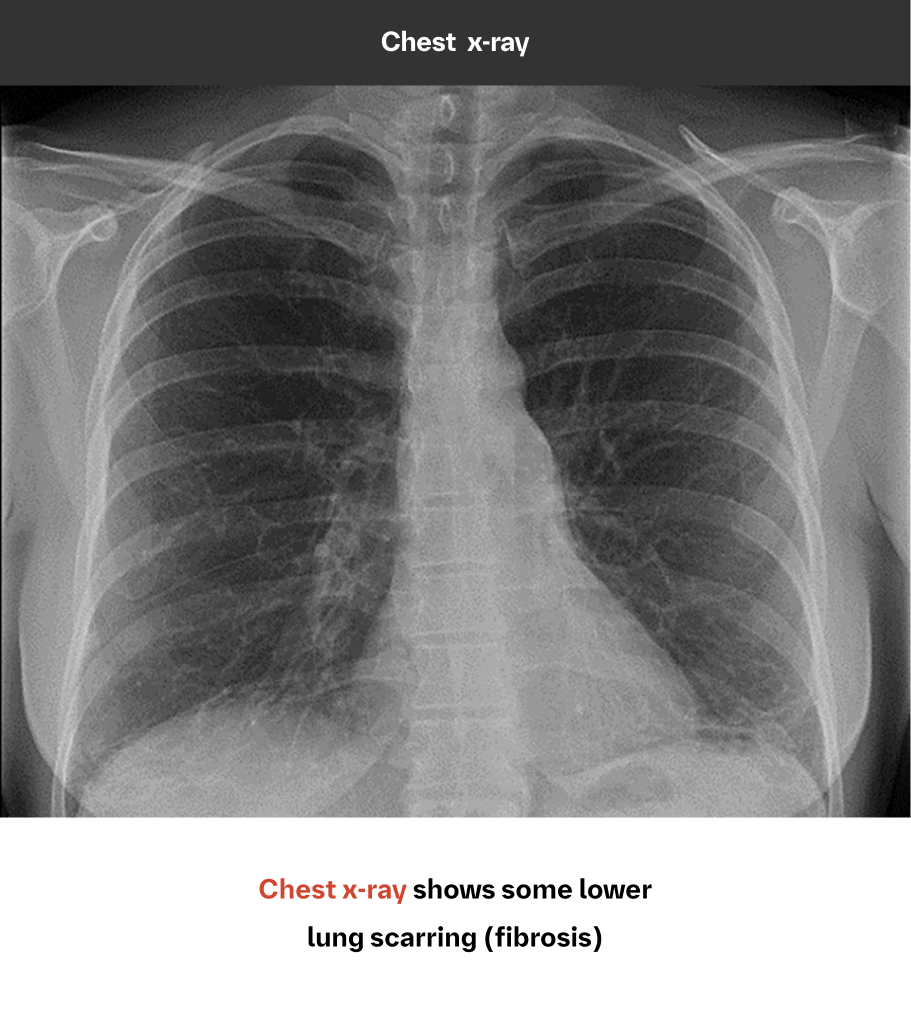

While chest x-ray is not sensitive for ILD diagnosis, it can play a role in identification9,10

Because HRCT provides a more accurate picture of the lungs than chest x-ray, it is considered the standard in diagnosing ILD. However, chest x-ray can detect pulmonary abnormalities and complications, and may even show signs of ILD prior to the development of symptoms or physiological impairment.

An abnormal chest x-ray is often the first indication of ILD

Case study used with permission from the American Thoracic Society.

Image and case study courtesy of, and used with permission from, Lydia Chelala, MD.Findings on chest x-rays suggestive of ILD may include features of interstitial changes and/or airspace disease, such as10-12:

- Reticular lines or scarring

- Volume loss, hilar retraction, or architectural distortion

- Honeycombing

- Nodules

- Ground-glass opacification or air bronchograms

- Cysts or cystic change